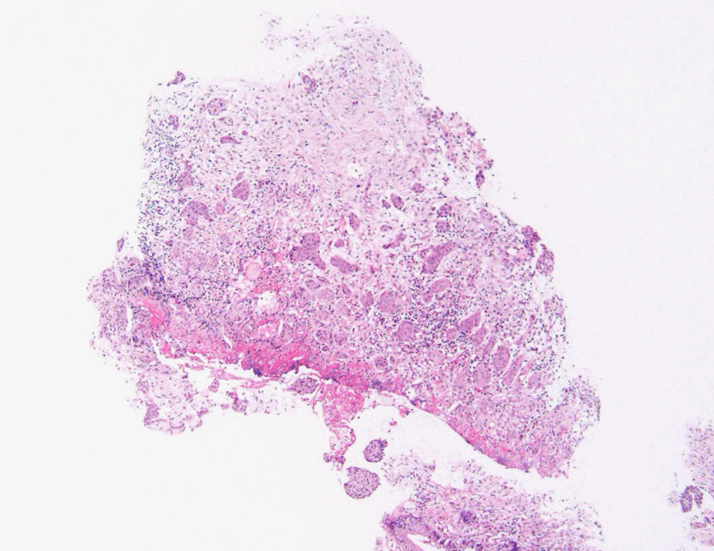

S状結腸粘膜生検組織所見:

粘膜筋板直下に小型胞巣を作って浸潤し炎症性の間質をともなう。 浸潤性増殖のわりに細胞は均一, そんなに異型性も強くない。apoptosisに陥った細胞が散在する。部位によっては胞巣状増殖細胞は細胞間橋がありそうな扁平上皮様に見える。深いところは線維性間質が増えてきて細胞は索状となりcarcinoidなども鑑別候補となるかもしれない。明らかな腺管形成, 粘液産生はみられない。35歳男性, わりとおとなしい扁平上皮癌様の組織か?と生検初見時に考えられた。desmoplasticな間質にもよく観察するとバラけた細胞異型が認められる。 (腫瘍胞巣①, ③)

腫瘍胞巣①腫瘍胞巣②腫瘍胞巣③深い部分